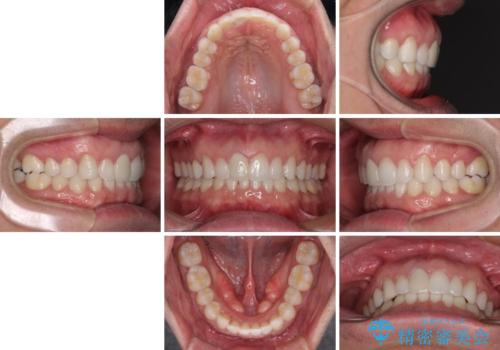

口が閉じにくい インビザラインによる矯正治療

- 口の閉じにくさを気にして来院された患者様です。

患者様と相談の上、横顔の印象から抜歯矯正は必要ないと判断し、IPR(歯と歯の間)並びに歯列全体の後方移動により口元の突出感の改善することとしました。

しっかりと装着時間を守り、ゴムかけも徹底していただいたので、思いの外口元を引っ込めることができました。

これ以上の改善を望まれましたが、非抜歯矯正でこれ以上口元を引っ込めると食いしばりすやすい咬合となるため、この歯列で終了としました。